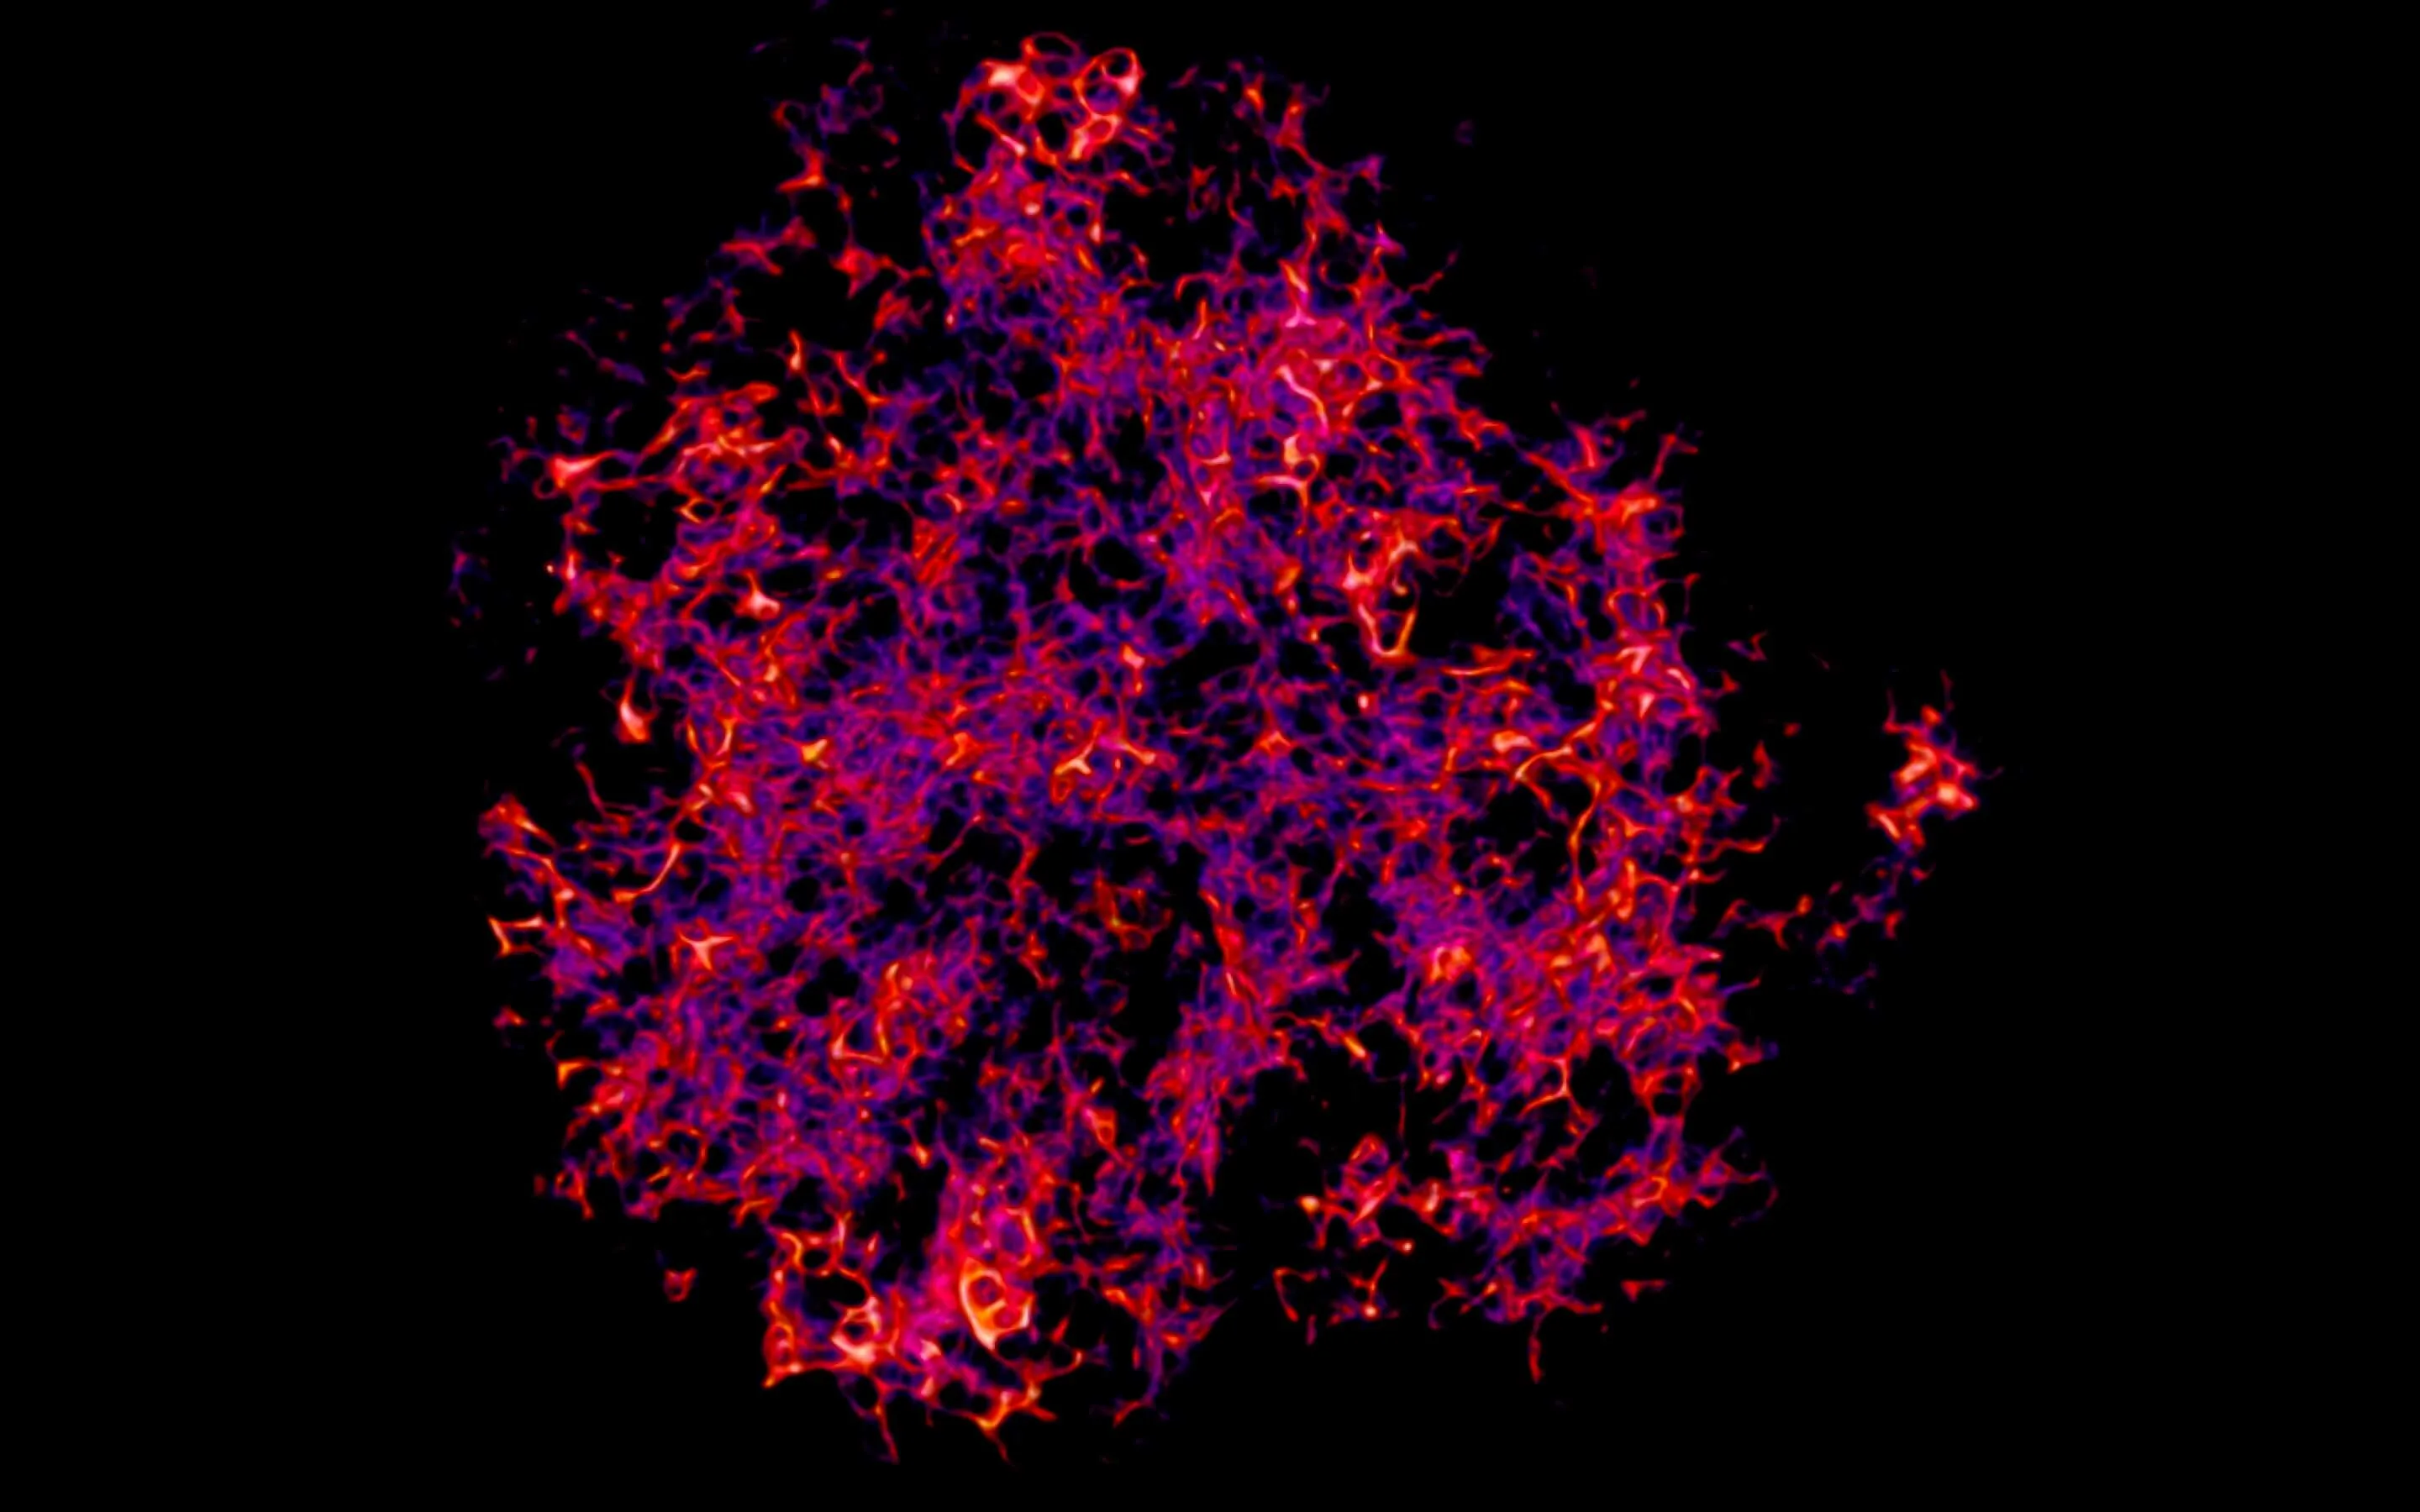

High-dimensional image analysis

To analyze complex tissues such as germinal centers, we use advanced microscopy techniques that generate large, multi-channel datasets. Manual analysis of these datasets is time-consuming and prone to bias. Therefore, we are developing computational pipelines that leverage machine learning and image analysis tools to segment and classify cell types, as well as quantify biologically relevant proteins and glycans within these tissues. This approach enables us to efficiently extract meaningful biological insights from high-dimensional imaging data. Use the slider to compare a raw microscopy image (left) with the corresponding segmented and classified image (right), generated by our analysis pipeline.